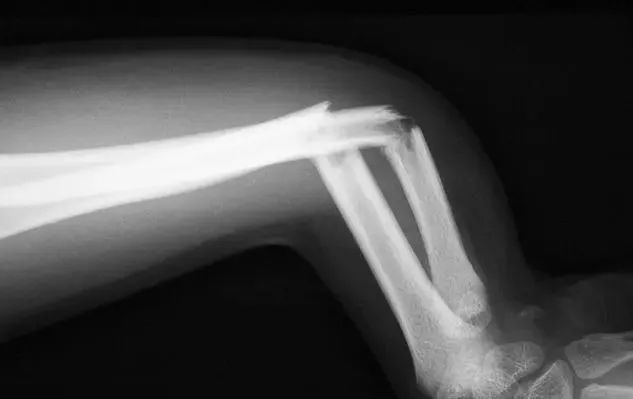

当你发现骨折时,你必须首先判断伤口的类型。因为骨折有不同的情况,如果是开放性伤口,你必须先处理伤口问题。骨折引起的开放性伤口损伤较大。除了损伤周围的组织和肌腱外,还会导致局部血管破裂和断裂。这种情况会导致大出血。如果出血量高,应及时进行止血治疗。但是,在包扎伤口时,应注意包扎的强度和局部组织问题。如果太紧,很容易导致组织缺血和坏死,如果太松,就不能起到止血的作用。骨折的位置也相对重要,因为不同的骨折位置可能会损害不同的组织。例如,肋骨骨折可能损害肺部或干燥,而其他部位的骨折可能损害不同的神经和组织。如果是肋骨骨折,有必要判断具体的损伤位置,以防止患者进行过多的活动。四个部位的骨折应防止影响四肢的活动功能。如果你随意移动,切断血管、神经和肌腱将产生更大的影响。

骨折不能随意治疗。毕竟,在确定骨折部位和程度时进行复位或其他治疗是有害的。因此,在解决局部损伤时,应立即进行检查、x光检查或x光检查CT通过检查,可以有效地判断骨折的程度和类型,然后进行复位和石膏固定,可以帮助患者有效恢复。骨骼实际上非常脆弱。随着年龄的增长,骨骼中的钙不断流失,因此在生活中很容易骨折。当你发现骨折时,你不必太惊慌。骨折是创伤的常见表现。只要你不随意处理,就不容易影响患者未来的活动功能。及时合理治疗可有效恢复。